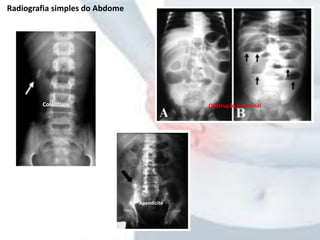

Radiografia simples do Abdome

Apendicite

Colelitíase Obstrução intestinal

• Raios Xde Tórax: • Radiografia simples do Abdome - Indicadas em pacientes que tem dor ou distensão abd. considerável ou que são suspeitos de obsTrução ou isquemia inestinal, víscera perfurada, cálculos renais ou ureterais ou colecistite aguda; - OBSERVAR: - padrão de gases nas vísceras ocas - Ar livre ou anormal sob o diafragma, dentro de canalículos biliares ou fora da parede intest. - Contorno dos órgãos sólidos - Linhas de gordura peritoneal - Densidades radiopacas - DISTENSÃO GASOSA é regra na OBSTRUÇÃO INTESTINAL - GÁS LIVRE SOB O HEMIDIAFRAGMA é típico nas ÚLCERAS PERFURADAS - DELINEAMENTO DO SISTEMA PORTA POR AR: PILEFLEBITE - AUMENTO DAS SOMBRAS RENAIS OU OBLITERAÇÃO DAS MARGENS DO M. PSOAS: DOENÇA RETROPERITONEAL Exames de Investigação

Radiografia simples doAbdome Apendicite Colelitíase Obstrução intestinal